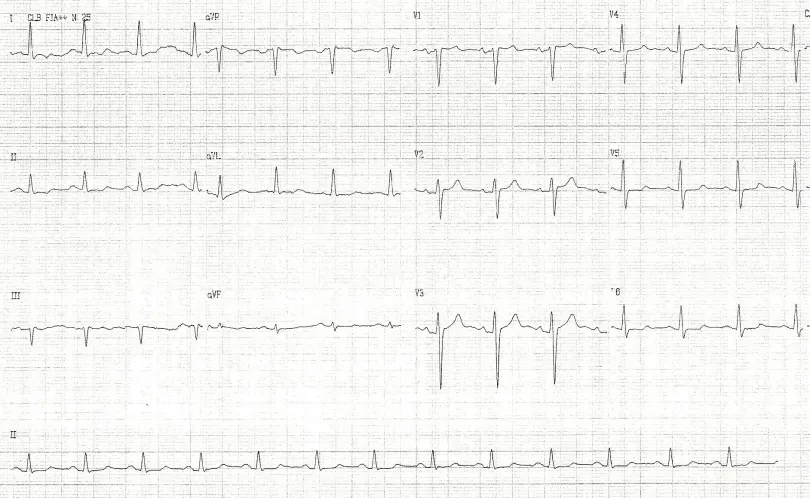

Distúrbios hidroeletrolíticos podem também alterar sua morfologia, como a hipercalemia, conforme mostrado na figura abaixo. Esse é o ECG de admissão de uma paciente com potássio de 10,2mEq/L. Notar que a onda T neste caso tem um aspecto apiculado ou em tenda. Além disto, observa-se outras alterações comumente bvistas na hipercalemia como o alargamento do complexo QRS e o achatamento da onda P. Tais achados são facilmente notados quando comparamos o primeiro ecg, em vigência de hipercalemia, como o segundo exame, após a normalização do potássio.

Dica: hipercalemia com alterações características de eletrocardiograma como vistas acima é considerada uma emergência médica. O paciente deve se monitorizado e além das medidas habituais para jogar o potássio do meia extra-celular para o intra-celular (ex: bicarbonato de sódio, glicoinsulina e inalação com beta agonista) e de expoliação do potássio corporal (furosemida, sorcal, etc) deve receber imediatamente gluconato de cálcio IV. Este não altera os níveis séricos de potássio mas estabiliza a membrana celular, atenunado as consequências eletrocardiográficas da hipercalemia, ao menos que momentaneamente.